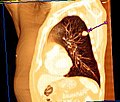

Der Unterschied zwischen der überlagerungsfreien Darstellung in der medizinischen Tomografie und einer Projektionsabbildung ist in den nachfolgenden Abbildungen illustriert. In Projektionsverfahren wie der Radiografie (gewöhnliche Röntgenuntersuchung) wird ein Schattenbild aufgenommen, auf dem sich mehrere Strukturen überlagern, wenn sie im Strahlengang hintereinander liegen. Beispielsweise überlagern beim konventionellen Röntgenbild die Weichteile der vorderen und hinteren Brustwand und die knöchernen Strukturen des Thorax die Lungenstrukturen. Dies würde die Diagnose eines Lungentumors (z. B. Bronchialkarzinom) erschweren. Jedes CT- oder MRT-Schnittbild vom Thorax zeigt dagegen nur eine 0,5 bis 10 mm dicke Schicht, die praktisch überlagerungsfrei ist.

Röntgenbild (Projektionsbild) eines kleinen peripheren Bronchialkarzinoms im linken Oberlappen -

Derselbe Tumor in der Computertomografie (axiales Schnittbild) -